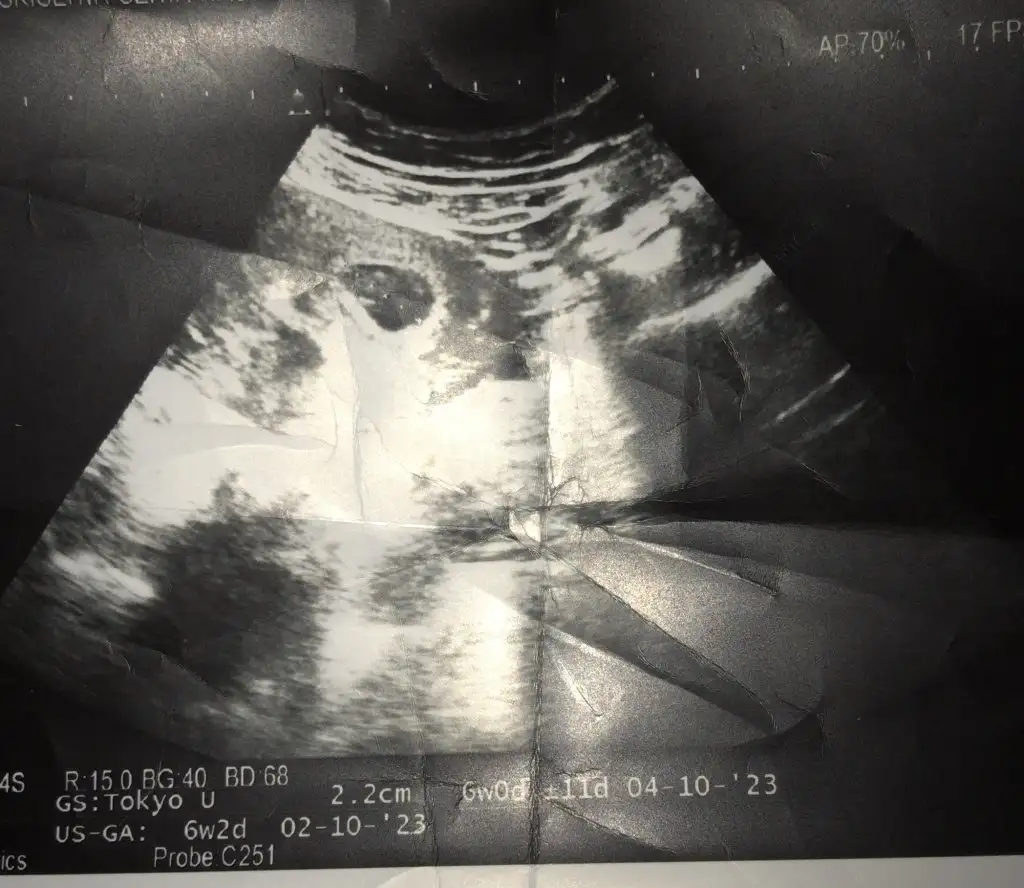

6+3 canım benimkinde bakabilir misin rica etsemMerhaba 6-8 haftalık fotosu var mı burda plesanta tam anlaşılmıyorda

Karından görüntüyse erkek vajinal görüntüyse kız :)6+3 canım benimkinde bakabilir misin rica etsem

Merhaba karından ultrasonda erkek vajinalse kız canım